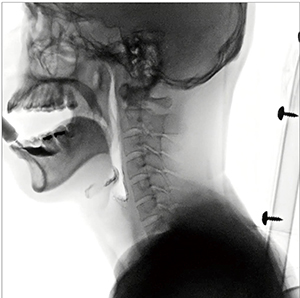

さらに、Astorex i9はX線管焦点-受像面間距離(SID)を110cmから最長180cmまで変動可能であり(図4)、嚥下造影ではSID延長により圧迫感が軽減し、作業スペースが確保しやすくなっている(図5)。

図5 SID延長を嚥下造影に活用

造影剤の動きが良好に描出される。

(パルスレート:15fps、線量モード:Normal)